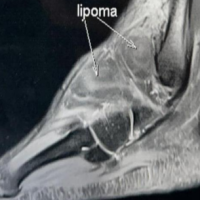

A 6-year-old female child, known case of KFS Type 2, was referred to the orthopedic service for evaluation and management of bilateral SD. She has a notable medical history, including short stature and intrauterine growth restriction at birth (birth weight: 2700 g). She is under regular follow-up for scoliosis and has undergone a right inguinal herniotomy in the past. The diagnosis of KFS was confirmed by genetic testing, revealing a homozygous pathogenic variant in the MOXI gene. Family history is significant for a male sibling with a confirmed diagnosis of KFS and a variant of uncertain significance in the AP3B2 gene. Examination revealed bilaterally elevated scapulae with limited abduction. Imaging, including computed tomography, revealed bilateral SD, more pronounced on the left side, characterized by elevated and axially rotated scapulae. There are bilateral omovertebral bones seen at the C3–C4 level, appearing as short, well-corticated bony structures medial to the scapulae, with no bony fusion to the scapulae. In addition, there is a posterior cervical fusion at C3–C4, consistent with underlying KFS. No evidence of aggressive osseous lesions is seen. The remaining visualized upper chest and cervical structures are grossly unremarkable. After multidisciplinary evaluation, the patient was scheduled for bilateral Modified Woodward’s procedure.